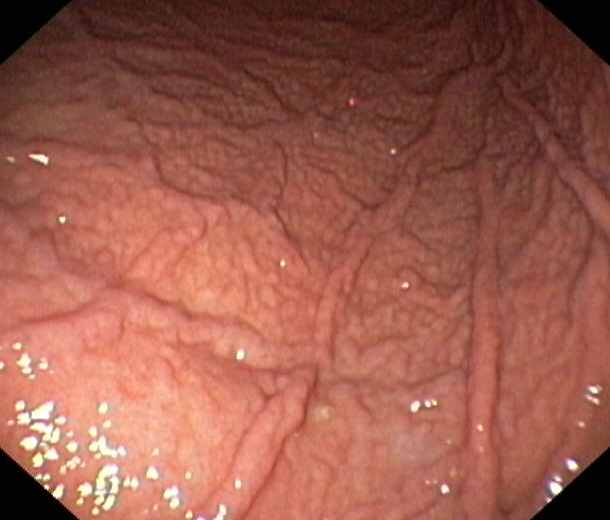

Gastritis caused by a chronic Helicobacter Pylori-infektion